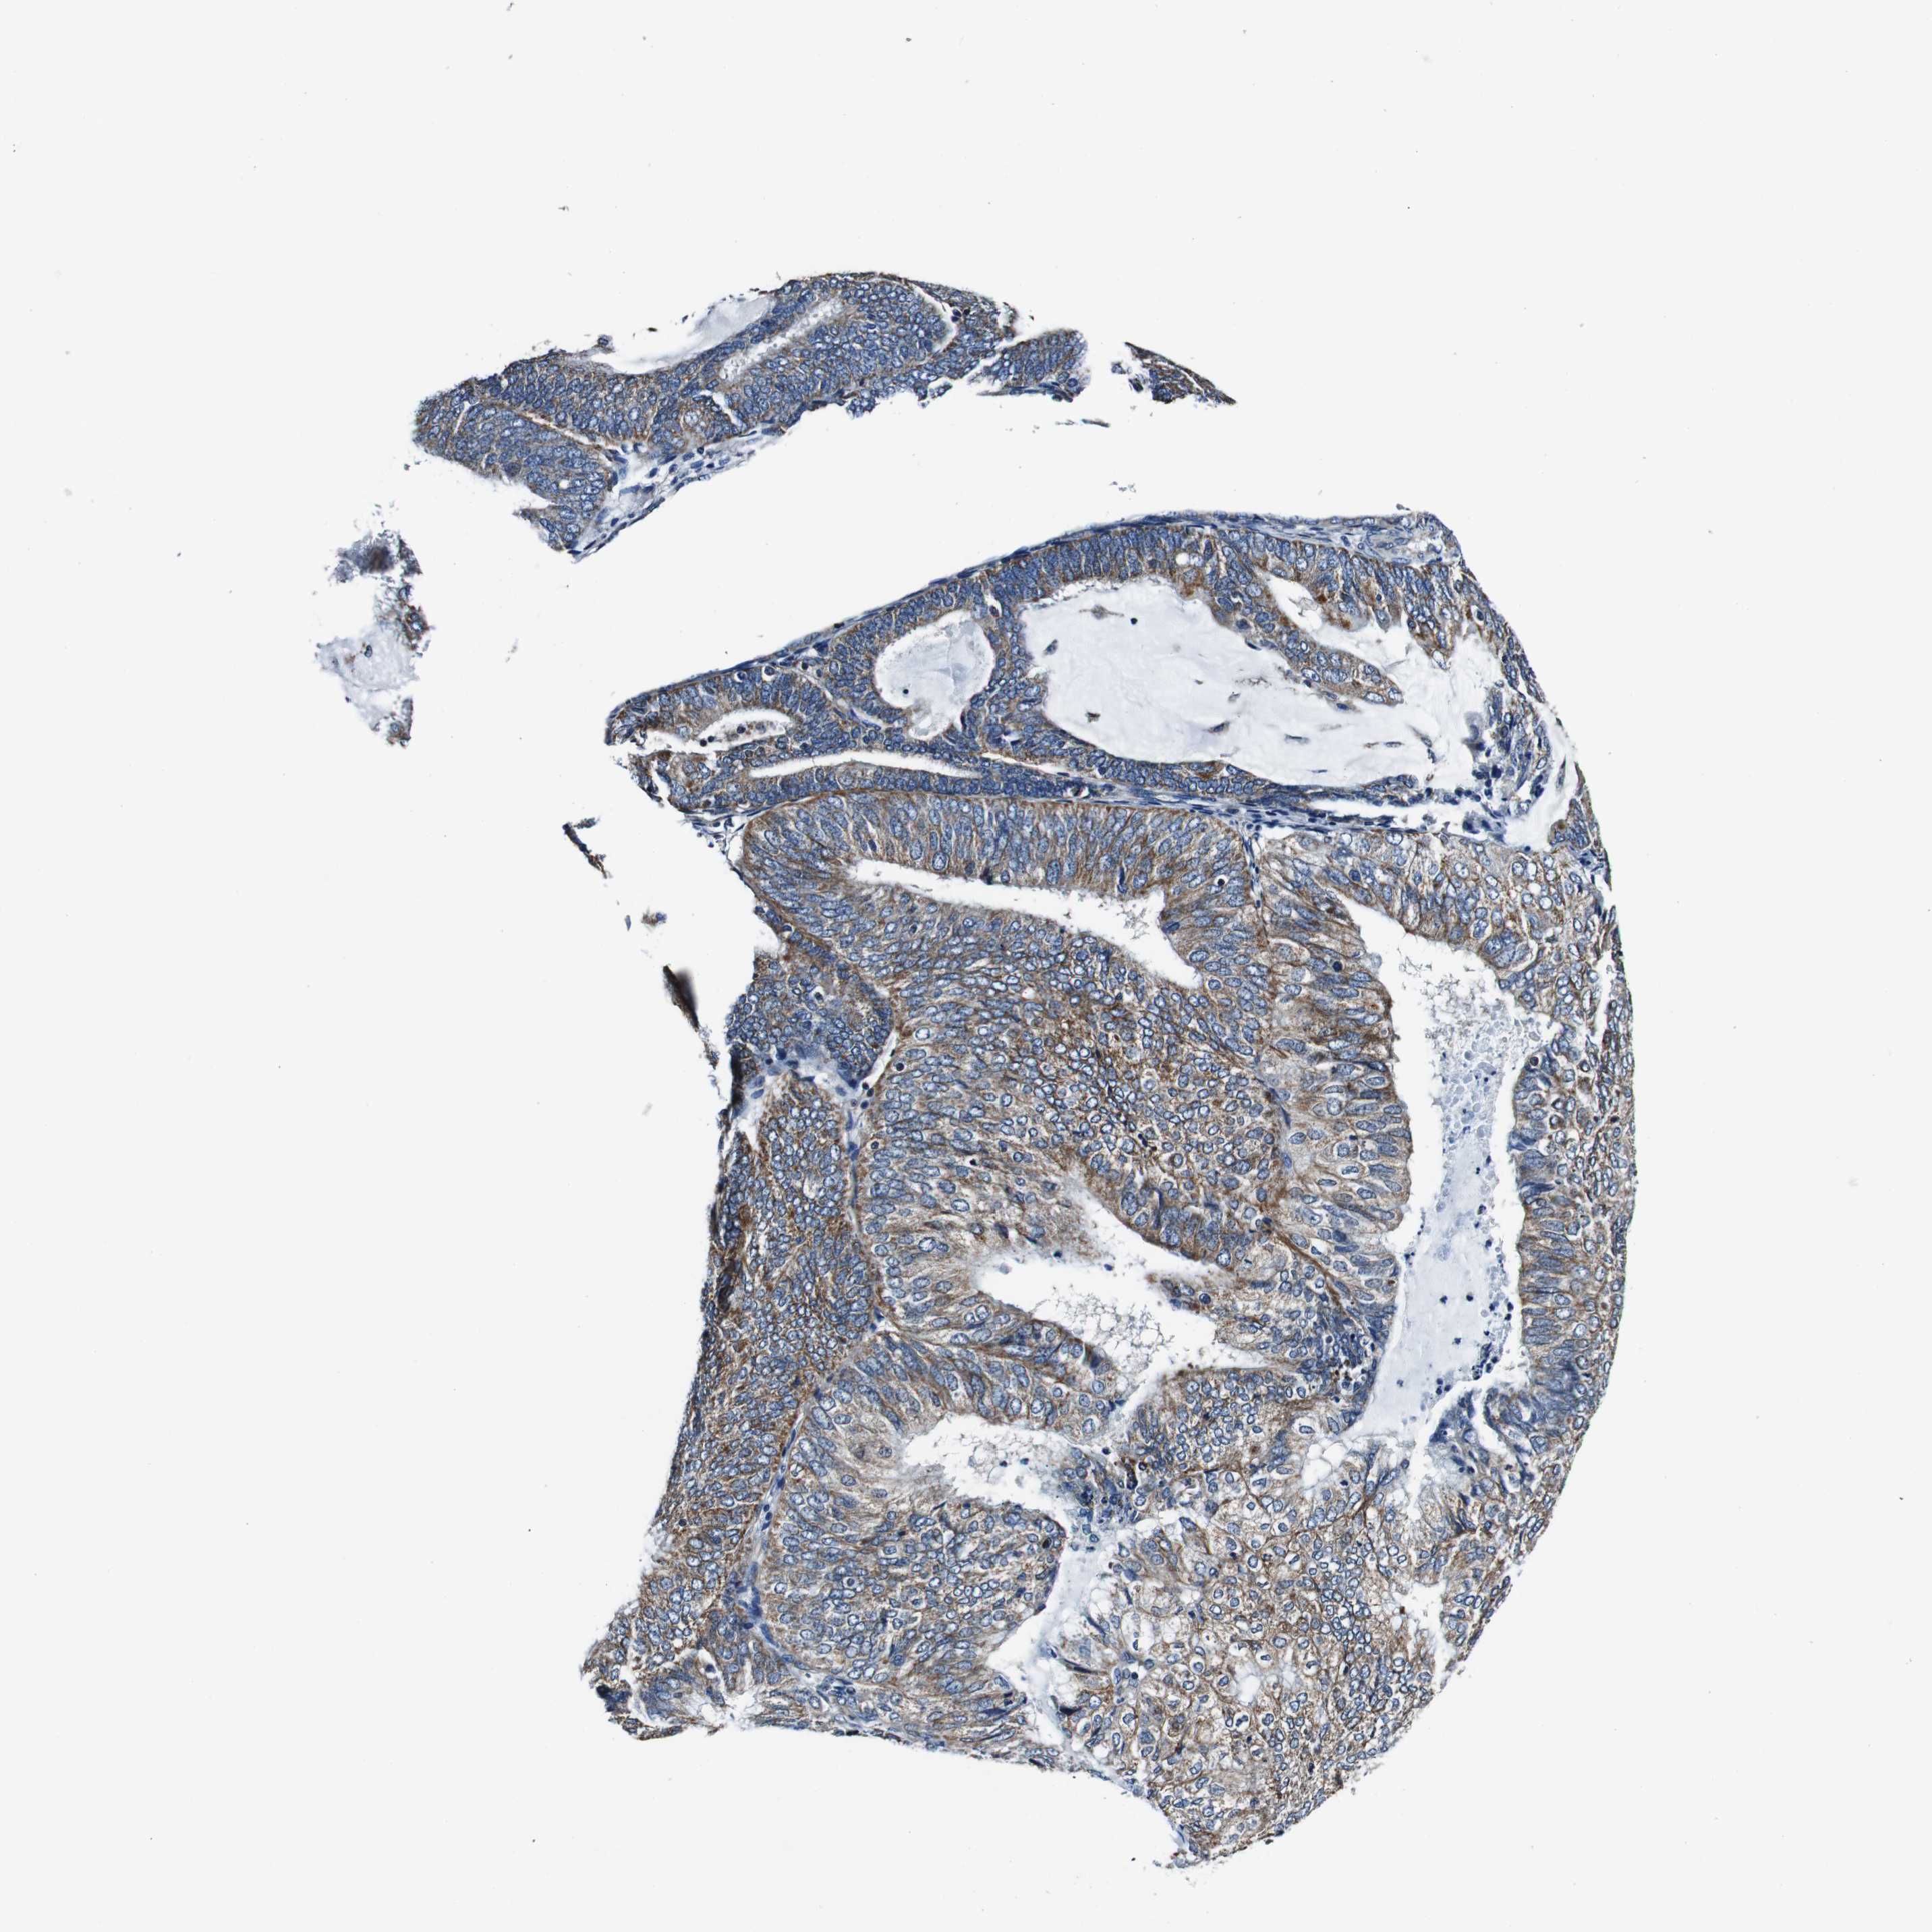

ENDOMETRIAL CANCER - Protein expressioni

A mouse-over function shows sample information and annotation data. Click on an image to view it in a full screen mode. Samples can be filtered based on level of antibody staining by selecting one or several of the following categories: high, medium, low and not detected. The assay and annotation is described here.

Note that samples used for immunohistochemistry by the Human Protein Atlas do not correspond to samples in the TCGA dataset.

Antibody stainingi

Antibody staining in the annotated cell types in the current human tissue is reported as not detected, low, medium, or high, based on conventional immunohistochemistry profiling in selected tissues. This score is based on the combination of the staining intensity and fraction of stained cells.

Each image is clickable and will lead to virtual microscopy that enables deeper exploration of all samples and also displays staining intensity scores, fraction scores and subcellular localization as well as patient and tissue information for each sample.

Antibody HPA007043

Antibody HPA007044

Antibody CAB010052

Staining

High

Medium

Low

Not detected

Intensity

Strong

Moderate

Weak

Negative

Quantity

>75%

75%-25%

<25%

None

Location

Nuclear

Cytoplasmic/membranous

Cytoplasmic/membranous,nuclear

Adenocarcinoma, NOS